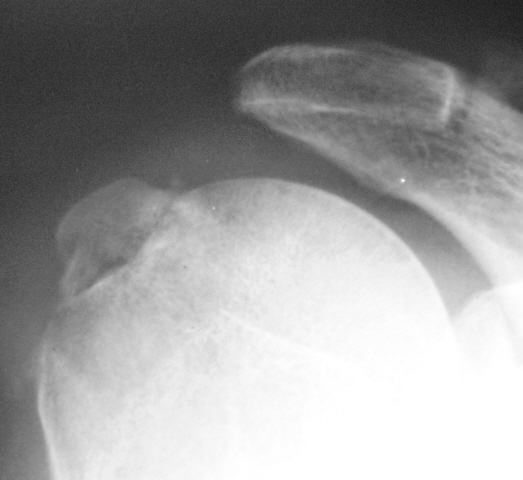

Вот то, что отмечено желтыми стрелочками на последней серии снимков - и есть отрыв большого бугорка. Такой большооооой отрыв большоооооооого бугорка.

Согласен с Вами Анна. "Ну очень большой".

С большим бугорком более-менее понятно. Вопрос: где малый?